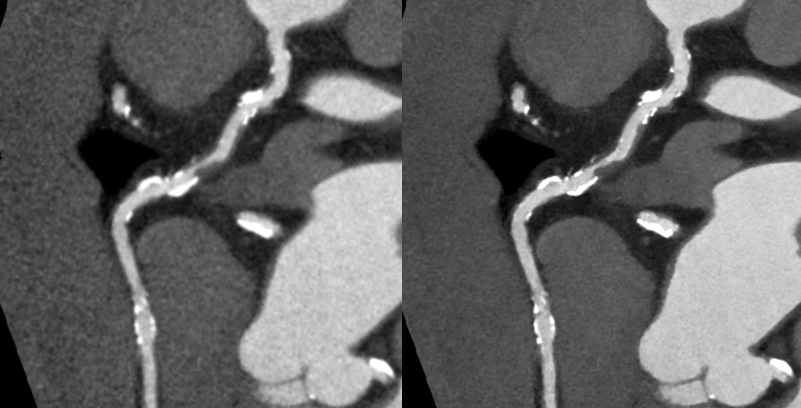

高精細画像再構成

当院で稼働中の320列CT装置2台をバージョンアップし、これまで以上の高精細なCT画像が得られるようになりました。

CT装置の解像度は、主にハードウエアの構成に依存するため、それ以上の高精細な画像を得ることが出来ませんでした。しかしながら、近年注目されている深層学習(ディープラーニング)による画像構築技術を用いて、最も高精細なCTで撮影された画像を教師画像とすることで、これまでの解像度を超える画像が得られるようになりました。

キヤノンメディカルシステムズが開発したPrecise IQ Engine(PIQE)によるディープラーニングの画像によって、冠動脈CT検査で評価が難しい石灰化やステントに接する部分の描出が向上されるため、さらに正確な画像診断が可能となりました。

ステント症例:左の従来画像と比較して,右の高精細ディープラーニング画像では小さなステントの内部も明瞭に描出されています。